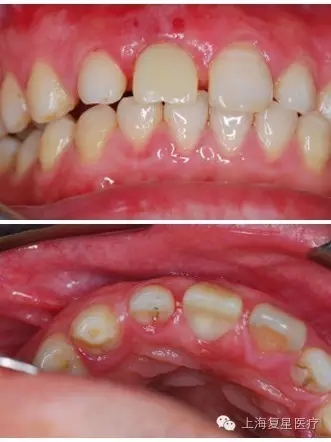

前牙即刻修復(fù)病例一例